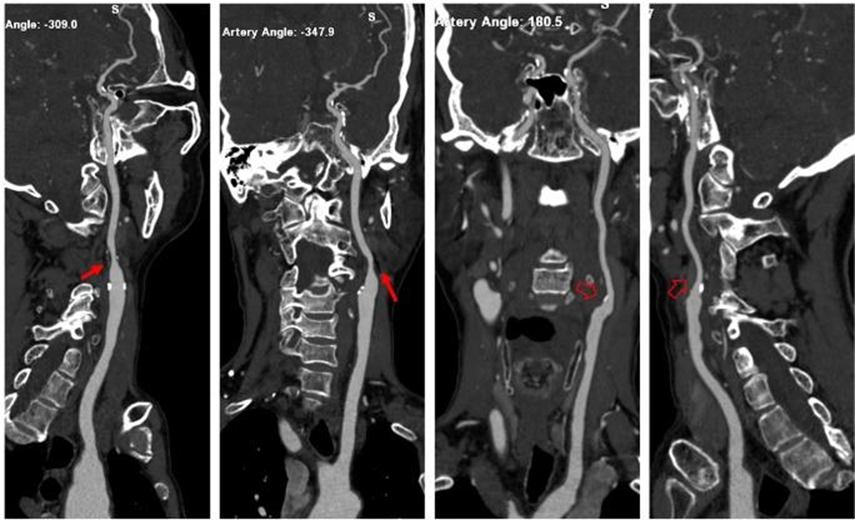

右侧颈内动脉起始部闭塞:三维图像颈内动脉未见显影,横断图像颈内动脉管腔内未见到高密度造影剂充盈。

左侧颈内动脉起始部混合密度斑块,管腔中度狭窄(红箭);右侧颈内动脉起始部钙化密度斑块,管腔轻微变窄(空心箭)。